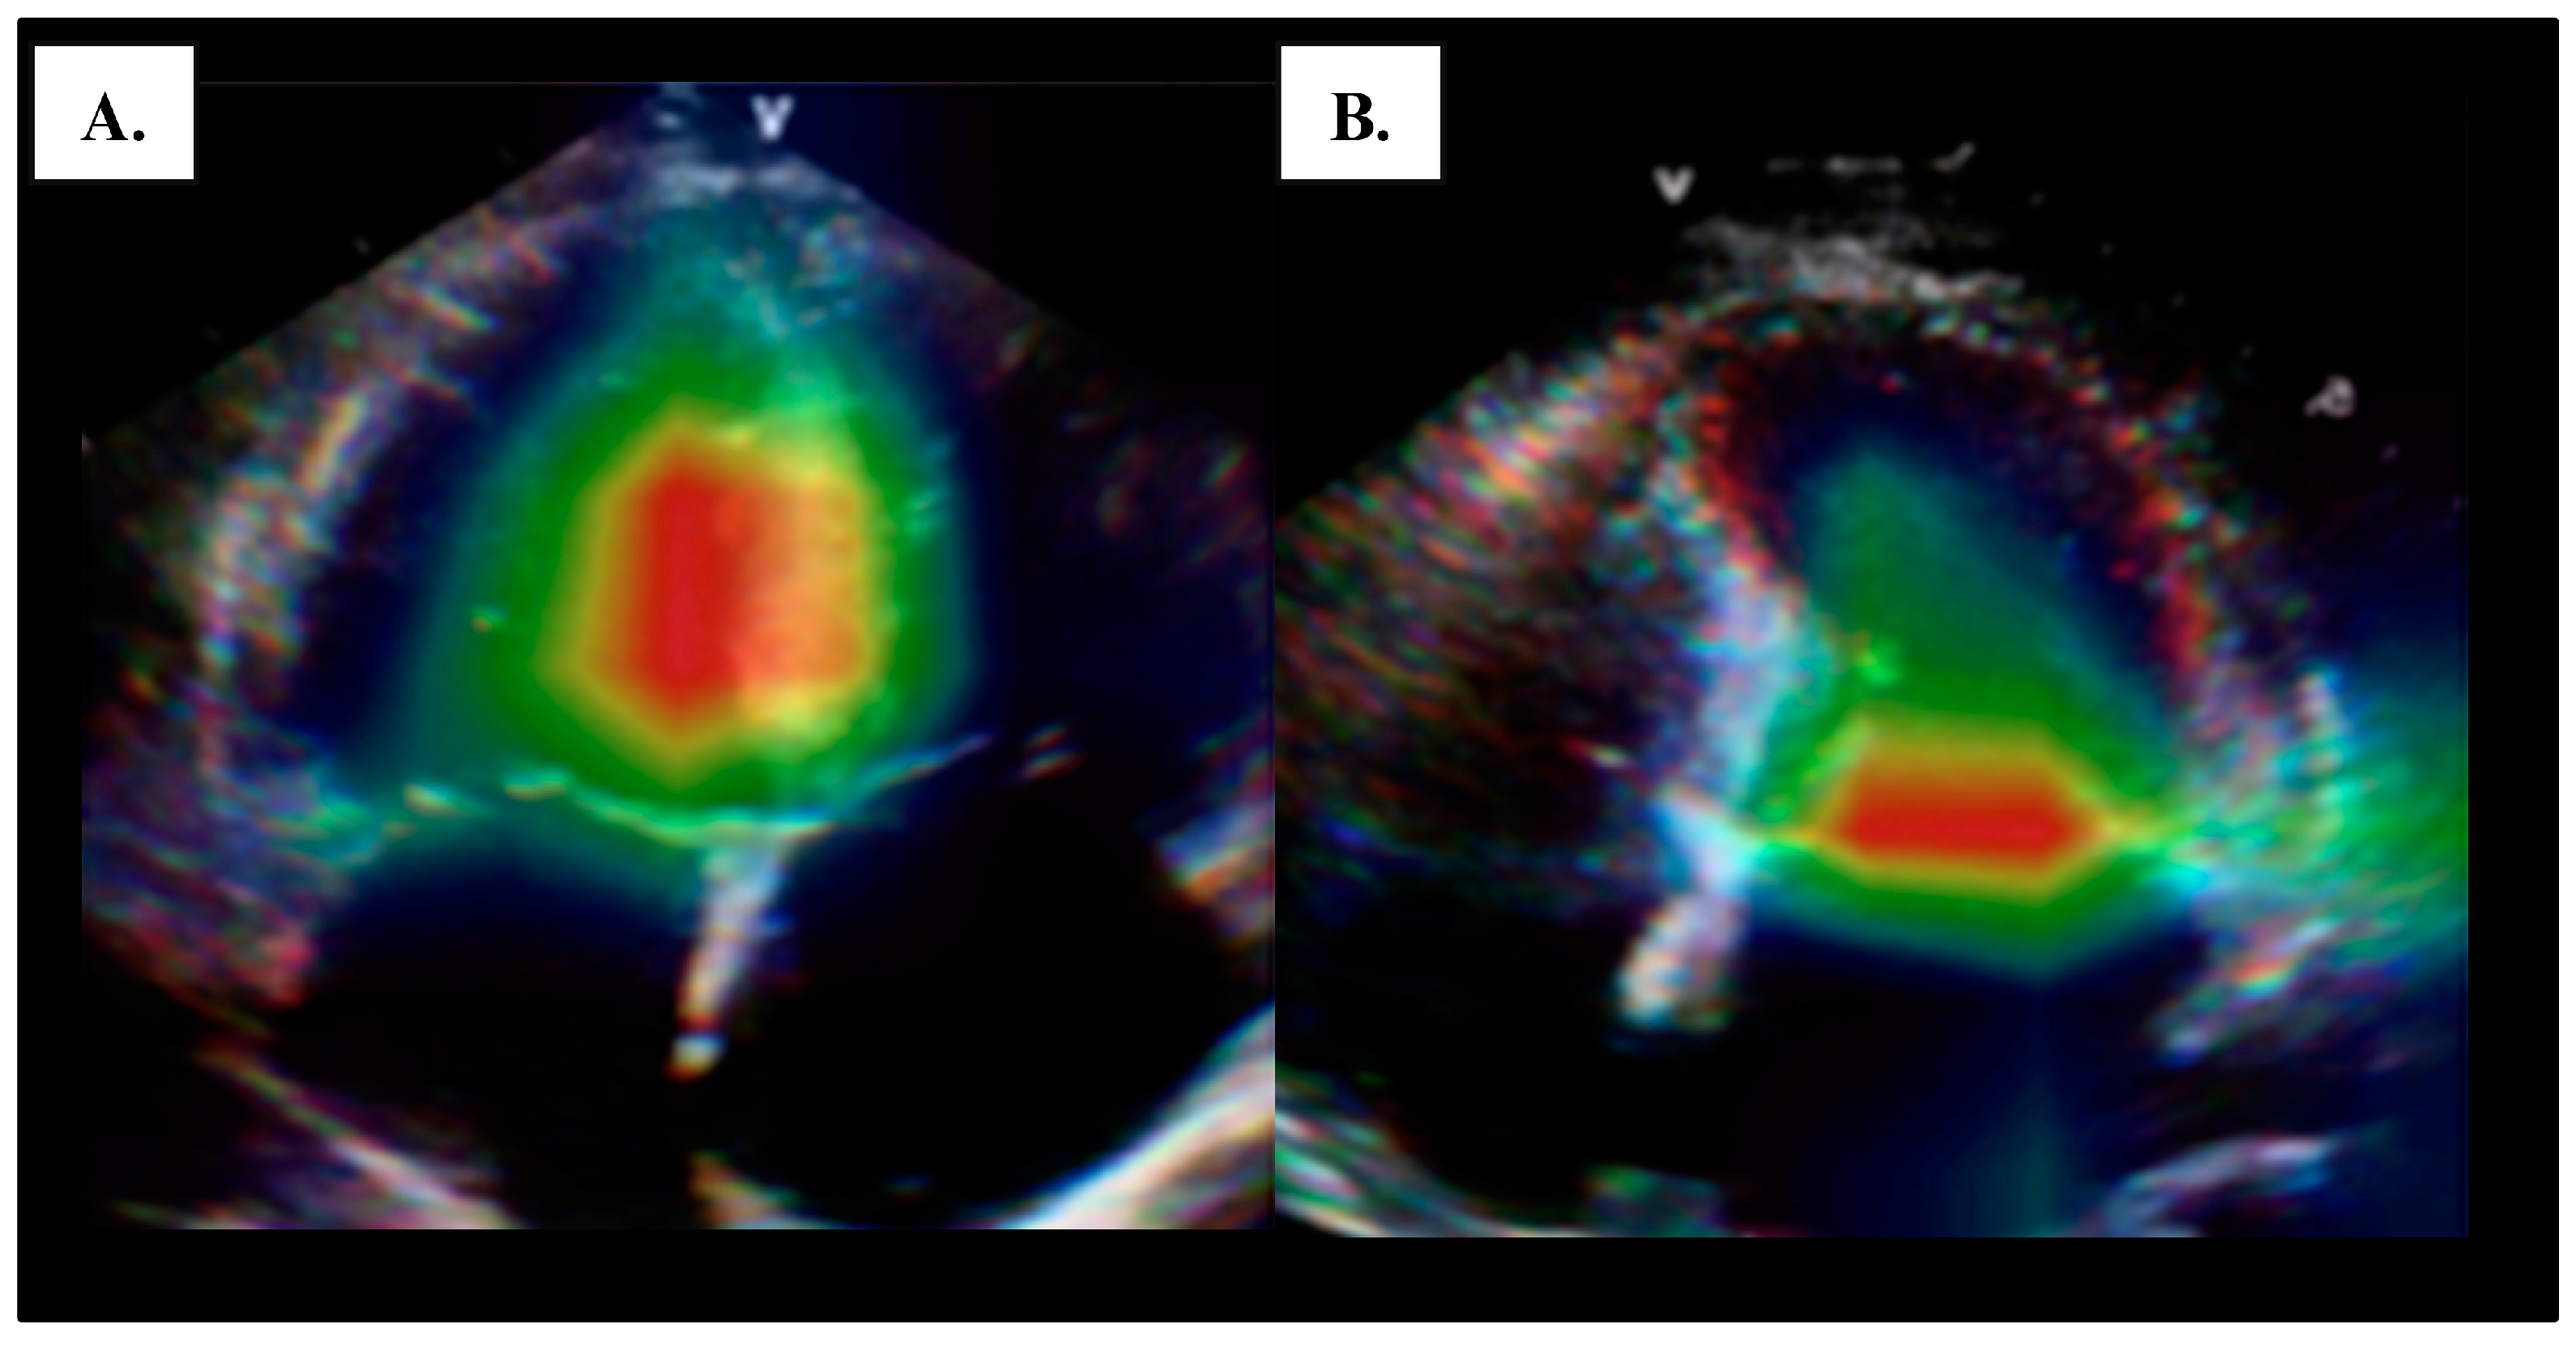

4.1. Left Ventricular Systolic Function

- Barry, T.; Farina, J.M.; Chao, C.J.; Ayoub, C.; Jeong, J.; Patel, B.N.; Banerjee, I.; Arsanjani, R. The Role of Artificial Intelligence in Echocardiography. J. Imaging 2023, 9, 50. [Google Scholar] [CrossRef] [PubMed]

- He, B.; Kwan, A.C.; Cho, J.H.; Yuan, N.; Pollick, C.; Shiota, T.; Ebinger, J.; Bello, N.A.; Wei, J.; Josan, K.; et al. Blinded, randomized trial of sonographer versus AI cardiac function assessment. Nature 2023, 616, 520–524. [Google Scholar] [CrossRef] [PubMed]